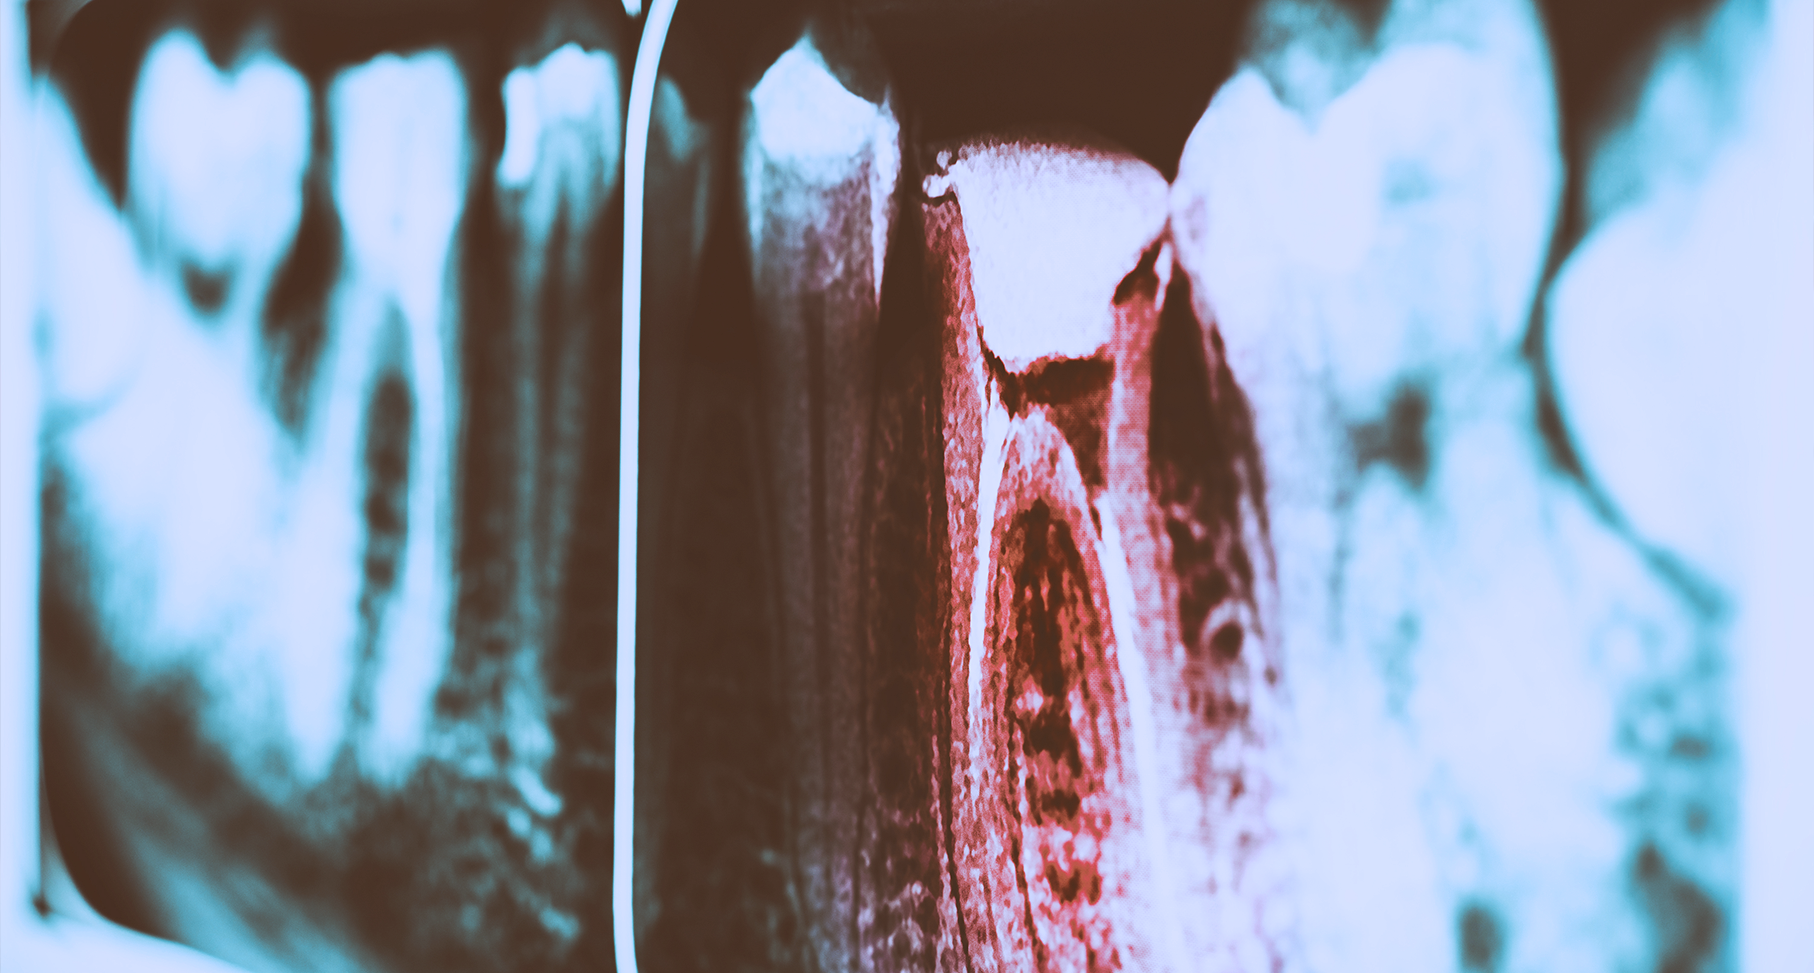

Η ενδοδοντική θεραπεία είναι γνωστή και ως “απονεύρωση”.